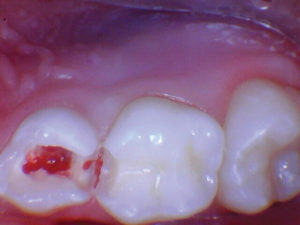

Caso 1

Un paciente de 8 años presentó descomposición de OD en un primer molar primario con síntomas de pulpitis reversible. El diente fue el tratamiento planificado para una restauración de OD con Activa Bioactive Restorative (Pulpdent). Tras la excavación por descomposición, se produjo una exposición pulpar que requirió una pulpotomía terapéutica. Debido a la edad del paciente, me sentí cómodo con una pulpotomía terapéutica con Biodentine (Septodont) seguida de una restauración estética. Si el paciente hubiera tenido entre cuatro y cinco años, me habría restaurado con una corona de acero inoxidable debido a su historial comprobado de longevidad.

Figura 1 Vista preoperatoria del primer molar primario superior. |